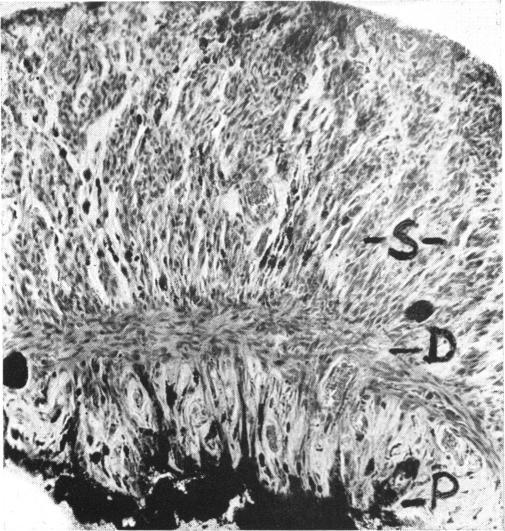

Heath P

Trans Am Ophthalmol Soc. 1951;49:147-66.